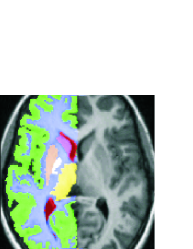

The ground truth data for this set consisted of dense (pixel by pixel) binary tissue labels, the tissue classes being cerebral white matter, cerebral cortex, lateral ventricle, thalamus, thalamus proper, caudate, and putamen, also divided into left and right. Example labels are shown in Fig. 1a.

Refer to caption

(a)

(b)

Figure 1: Left: An example registered brain image, overlaid by its accompanying anatomical labels, for cerebral white matter, cerebral cortex, lateral ventricle, thalamus, thalamus proper, caudate, and putamen. Labels are also divided into left and right, one side only shown here. Center: The bounding circle (green), the warp control points (red), and control point displacements (yellow), scaled to show relative not absolute magnitude. Right: The resultant warped image, which has a mean displacement of d=3.0𝑑3.0d=3.0 pixels.